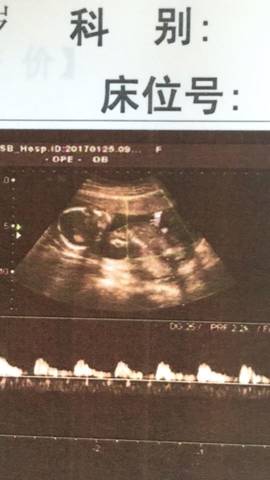

双顶径可以看男女,真的吗?

在民间有种说法是,双顶径减股骨长大于2,说明你肚子里面很大可能是男宝宝,小于2,说明你肚子里面很大可能...